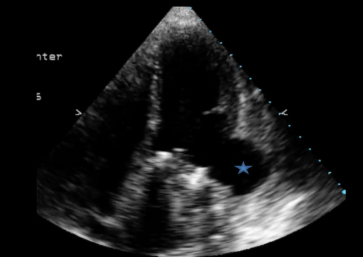

Ecocardiograma, evidenciando pseudoaneurisma (asterisco azul):